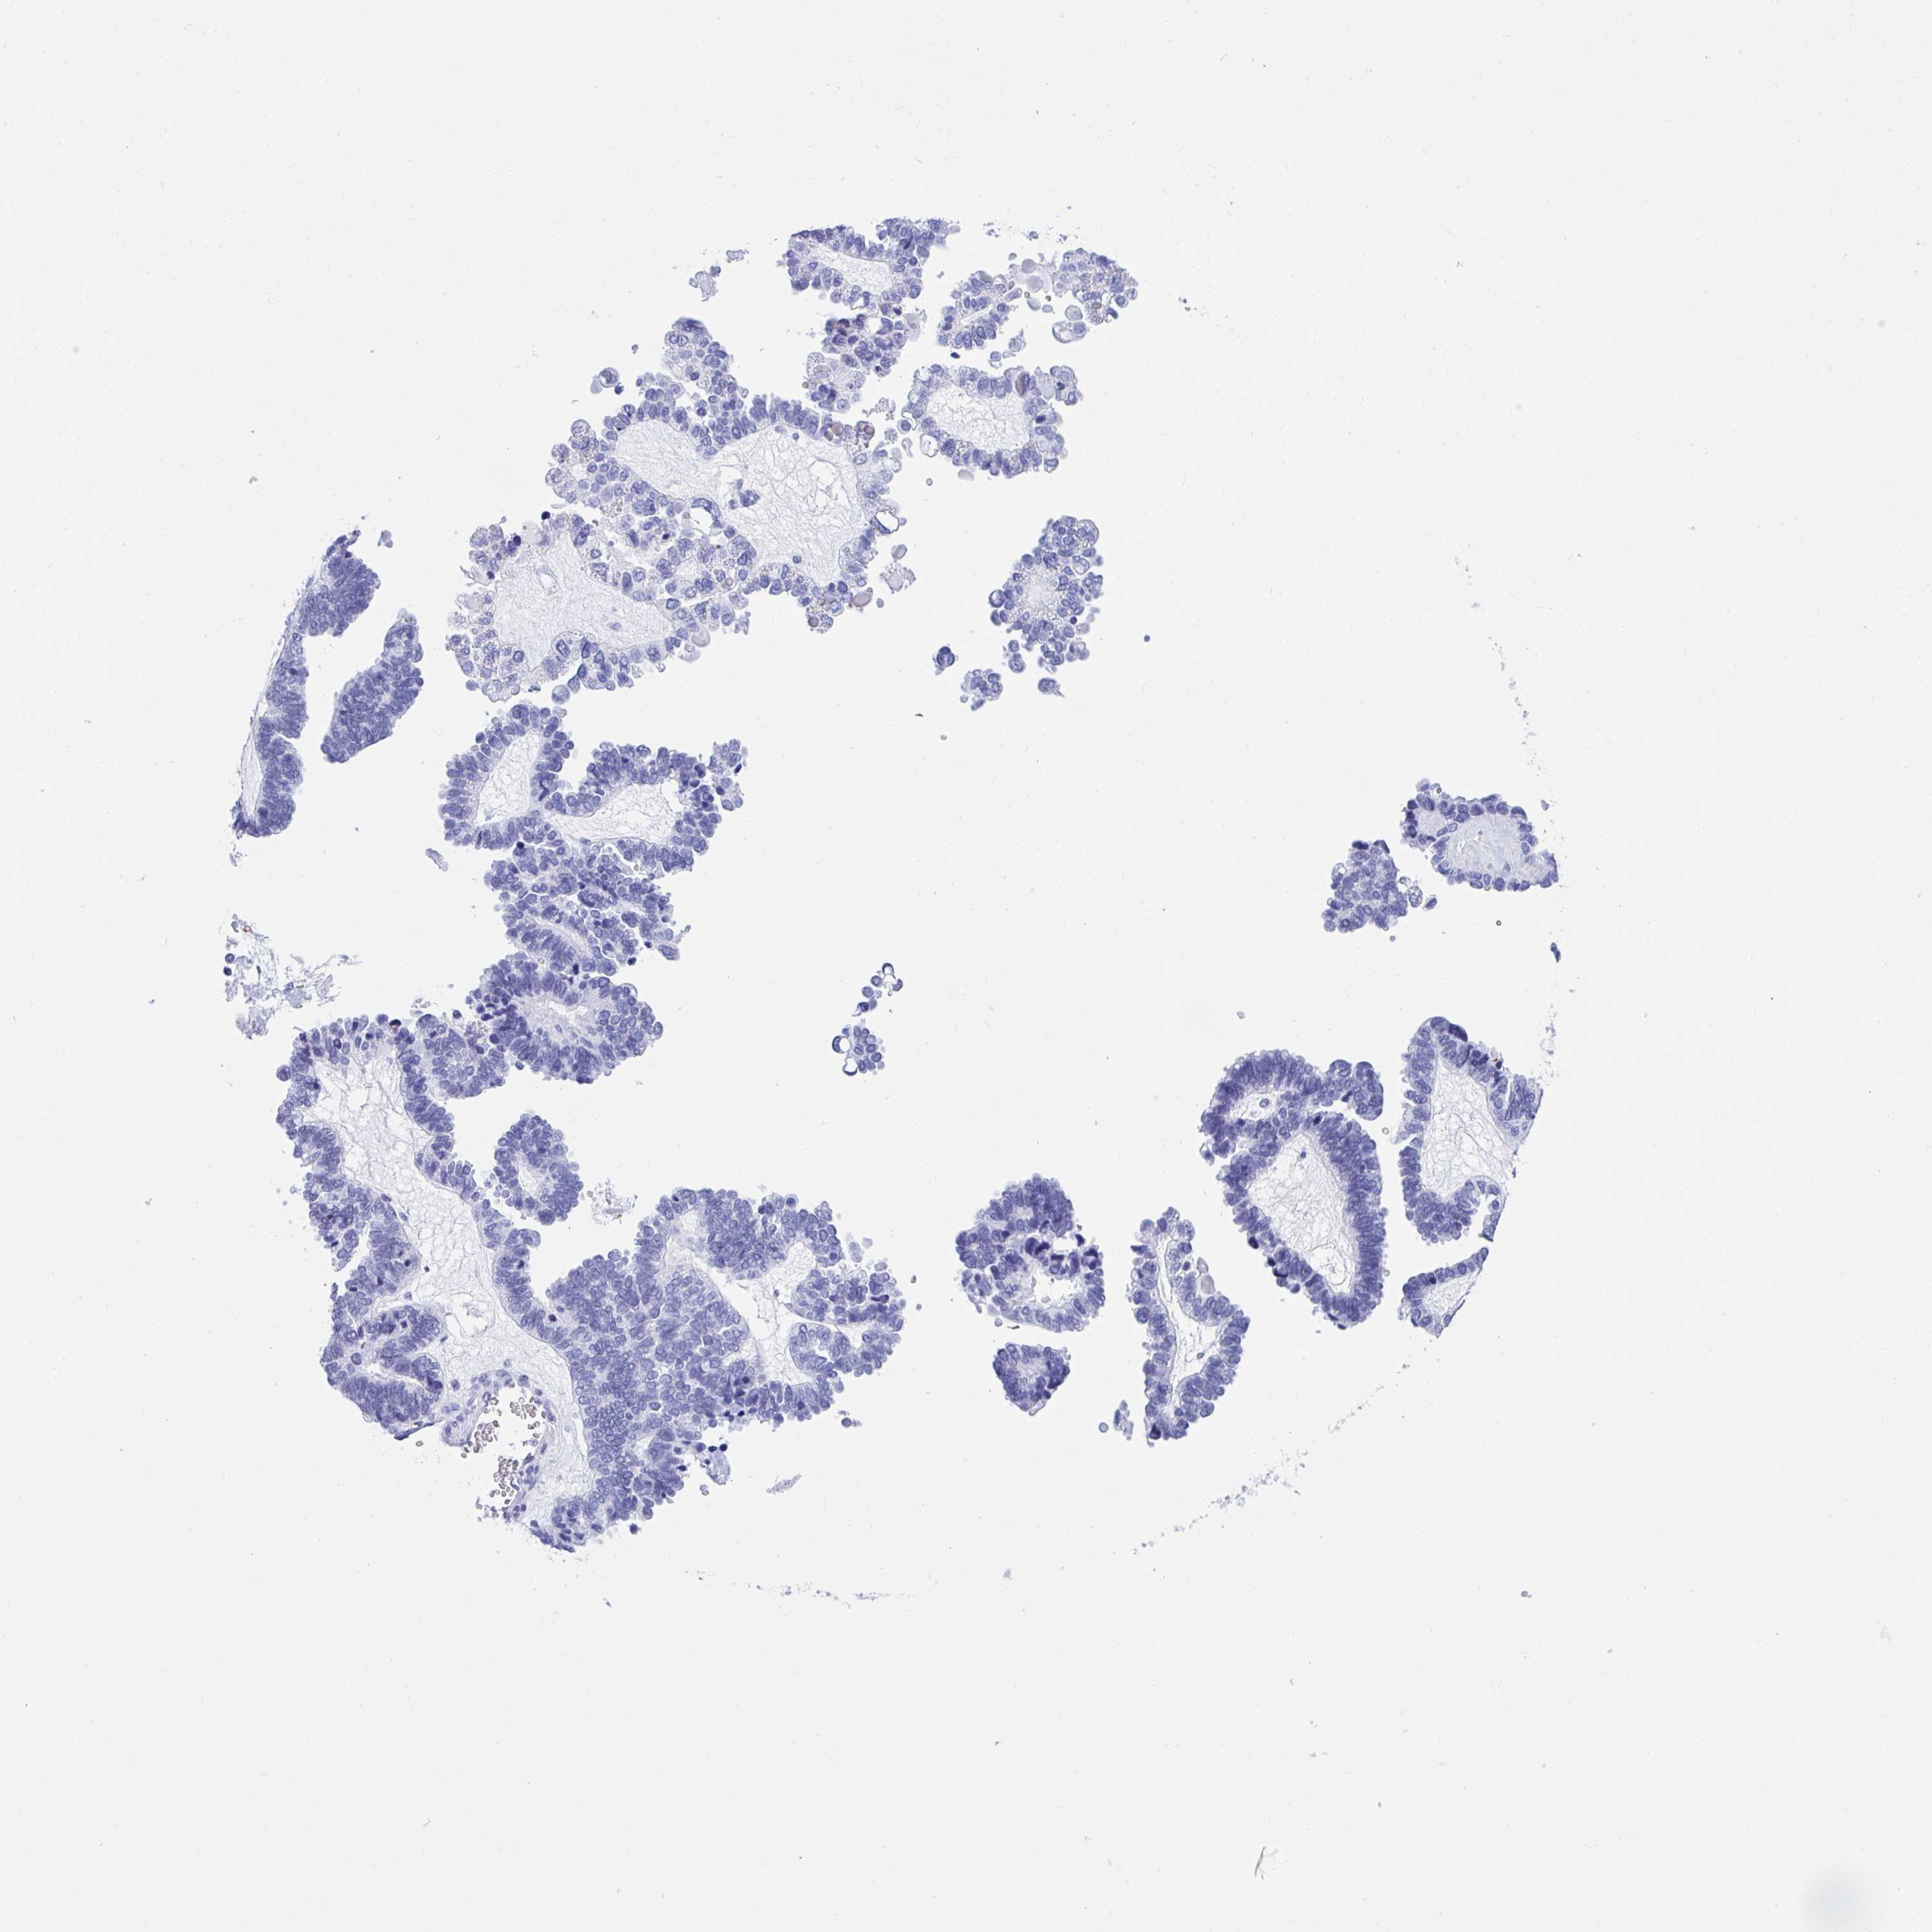

OVARIAN CANCER - Protein expressioni

A mouse-over function shows sample information and annotation data. Click on an image to view it in a full screen mode. Samples can be filtered based on level of antibody staining by selecting one or several of the following categories: high, medium, low and not detected. The assay and annotation is described here.

Note that samples used for immunohistochemistry by the Human Protein Atlas do not correspond to samples in the TCGA dataset.

Antibody stainingi

Antibody staining in the annotated cell types in the current human tissue is reported as not detected, low, medium, or high, based on conventional immunohistochemistry profiling in selected tissues. This score is based on the combination of the staining intensity and fraction of stained cells.

Each image is clickable and will lead to virtual microscopy that enables deeper exploration of all samples and also displays staining intensity scores, fraction scores and subcellular localization as well as patient and tissue information for each sample.

Antibody HPA004842

Antibody HPA056953

Cystadenocarcinoma, serous, NOS

Carcinoma, endometroid

Carcinoma, NOS

Cystadenocarcinoma, mucinous, NOS